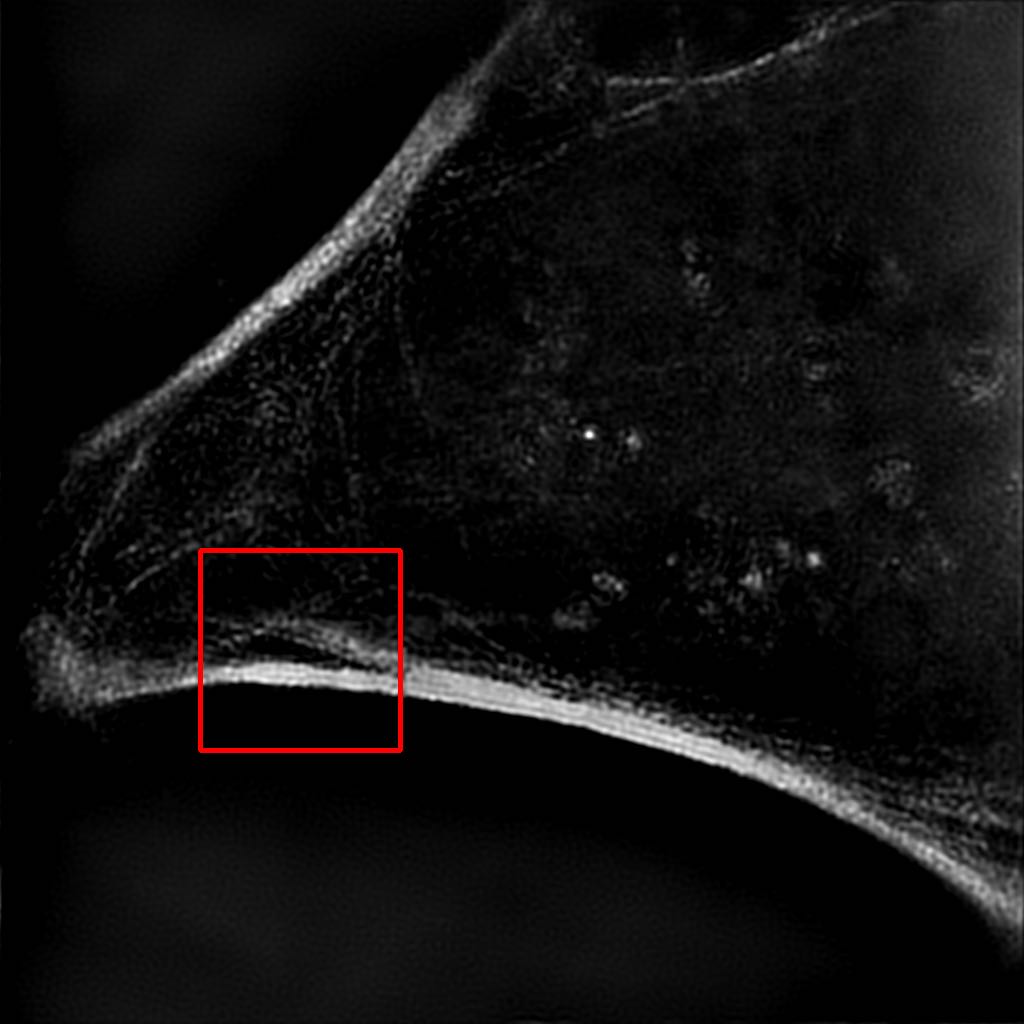

(a) Bicubic

(20.35 / 0.41)

Refer to caption

(b) Output

(24.96 / 0.741)

(c) SIM

a

Figure 8: Results of our algorithm on an unseen image in the W2S dataset [13]. (a) Low resolution widefield image upscaled using bicubic interpolation. (b) Output of our model in our final solution. (c) Corresponding image obtained using a SIM process. PSNR and SSIM values are, respectively, shown in parenthesis. Images on the second row are zoomed up regions highlighted by red boxes on the full images.

It can be observed in Figure 8 that, even though not perfect, the denoising is very effective and that the textures and details of the image are well approximated when compared to the ground truth SIM image.